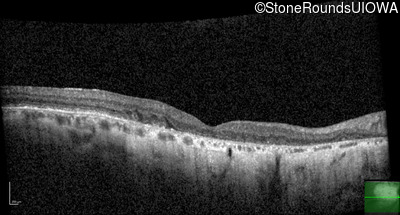

Age at visit: 57 years (Visit 2)